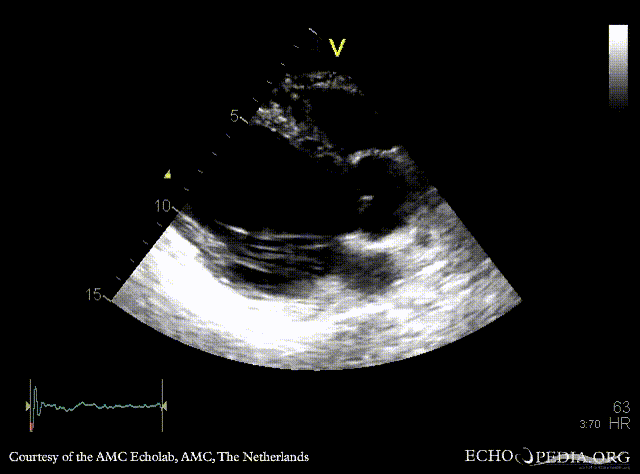

Infarction of posterior and inferior wall

Courtesy of: AMC Echolab, AMC, The Netherlands

E00526.gif E00527.gif

A4CH: akinesia of inferoseptal wall A2CH: akinesia of inferior wall